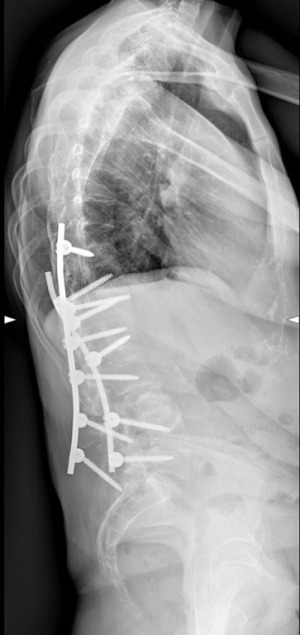

At 3-month post-surgery check-up, X-rays revealed that the spinal instrumentation had dislodged secondary to osteopenia and torsional forces. The left Co-Cr rod, due to its stiffness, which is higher than the titanium rod, was carrying higher forces onto the screws, which pulled the screws from L4 and L3 out of the pedicles (Figure 3). Revision surgery was performed, the loose screws were taken out and replaced in L4 and L5, and a new titanium rod was placed on this side. Cobb’s angle decreased to 42° after the surgery (Figures 4,5). The patient was discharged as no complications occurred.